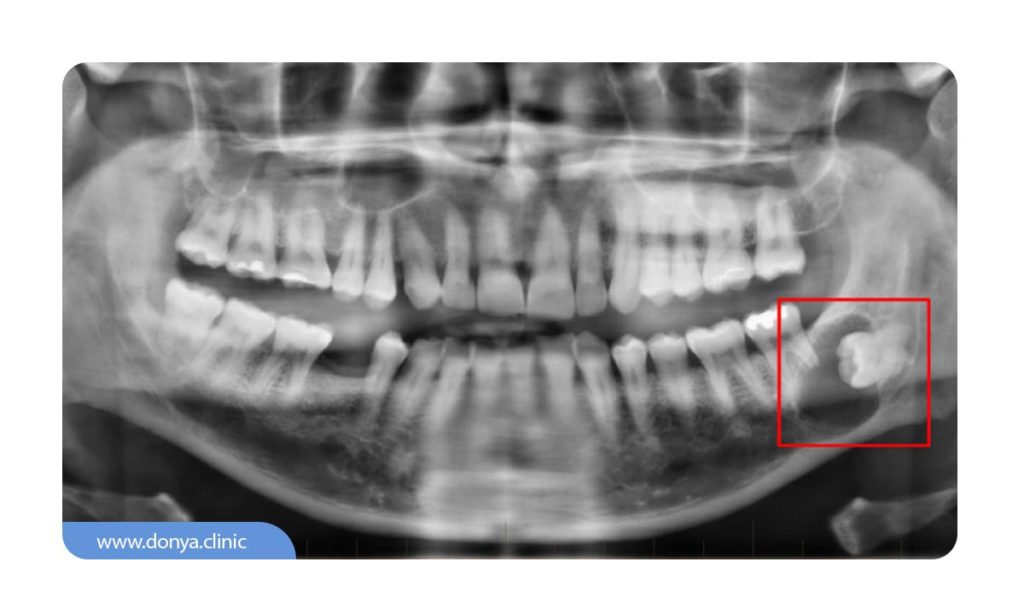

او پی جی یا OPG خلاصه شده عبارت (Orthopantomagram) نوعی اسکن دهان و دندان با کمک اشعه ایکس است که یک تصویر واحد از همه دندان ها در فک های بالا و پایین را به صورت یکجا نشان می دهد. به جز دندان ها، با کمک این عکس، نمایی از استخوان فک و مفصل گیجگاهی که محل اتصال استخوان فک به جمجه است به نمایش در می آید. ادامه مقاله را بخوانید تا با کاربردها، مزایا و هزینه عکس دندان opg بیشتر آشنا شوید.

با تصویربرداری او پی جی، می توان به خوبی مسائل و مشکلات مربوط به سینوس های فک بالا، موقیعیت دندان ها (برای ارتودنسی)، و سایر ناهنجاری های استخوان های فک را تشخیص داد. سایر کاربردهای عکس دندان opg تشخیص موارد زیر است:

در مقابل، عکس OPG یا ارتوپانتوموگرام، یک تصویر دوبعدی پانورامیک است که تصویر کاملی از تمام دندان ها در فک های بالا و پایین را ارائه می دهد. این روش بیشتر برای تشخیص مشکلات کلی دهان و دندان مانند نامرتبی دندان ها، بیماری های لثه و شناسایی دندان های پوسیده استفاده می شود.